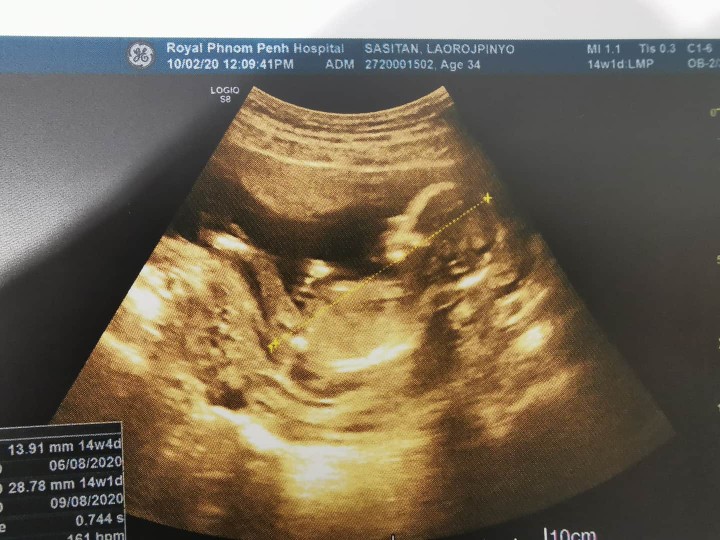

ตอนนี้ตั้งครรภ์ได้ 3 เดือนแล้วคะ

เห็นชัดมากเลย